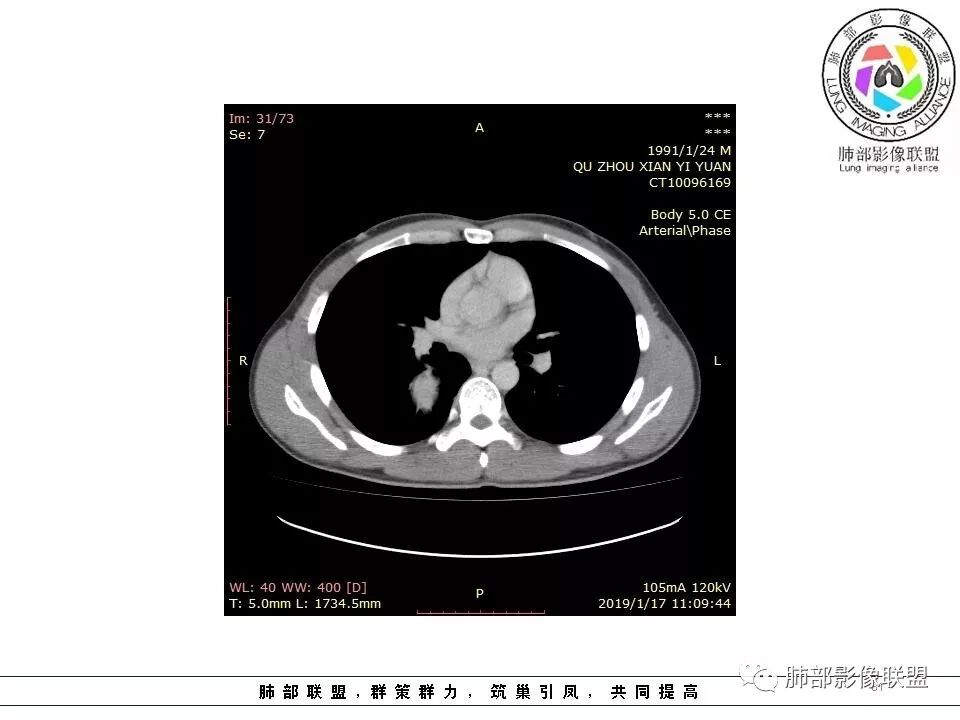

右后纵膈脊柱旁软组织占位,形态规则类圆,边缘光整,肺组织受压,胸膜尾,肋间动脉供血。中度不均匀延迟强化。

右后纵膈脊柱旁软组织影,与纵隔结构分界不清,形态规则类圆,边缘光整,肺组织受压,胸膜尾,肋间动脉供血。肺动脉推移,中度不均匀延迟强化。考虑神经来源,神经鞘瘤,神经纤维瘤二者不易鉴别。

病灶定位脏层胸膜,肺组织受挤压,有胸膜尾征,动脉期可见血管支配,考虑肺动脉供血,静脉期,强化增强明显,符合快进慢出特点,病灶内可见低密度区,考虑胸膜孤立纤维瘤。

青年男性,右侧脊柱旁软组织肿块,边缘膨隆,密度不均,临近肺组织受压、胸膜增厚,增强后动脉期呈不均匀强化,并可见肋间动脉供血,延迟期强化较均匀,定位肺外,首先考虑SFT,神经源性肿瘤待排

青年男性,右侧脊柱旁占位,瘤肺界限清晰,支气管推移,胸膜尾,D字征,胸膜下脂肪影,蛇纹血管,双重供血,延迟强化,定位胸膜,支持sft

肋间动脉供血,强化尚均匀,逐步强化

供血,体外供血,体循环,要么是壁层胸膜,要么胸膜外的,脏层胸膜应该是对内供血。病变里面的血管,除非是非常粗大迂曲的血管,不然,我不认为是其特点。

这个病人不是肺动脉与支气管动脉供血,是肋间动脉供血

1.右上胸内脊柱旁类圆形肿块,质地似乎比较坚实,密度稍显不均,但未显示明确的坏死。

2.肋间动脉病供血也提示肿块来自后纵隔?